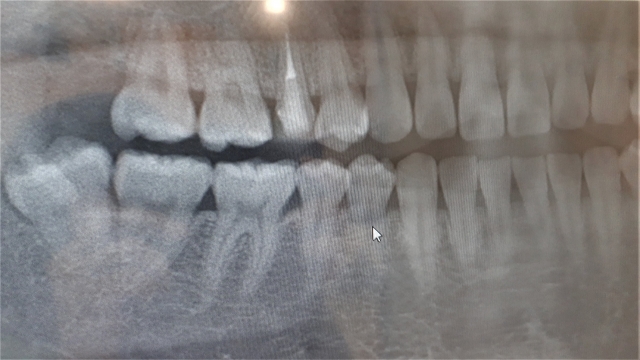

親知らずの抜歯が難しいと判断される背景には、主に歯の位置や向き、そして周囲の組織との関係が大きく関わっています。特に多いのが、歯が横向きや斜めに埋まっているケースで、このような状態では歯ぐきを切開したり、歯を分割して取り出す必要が出てきます。また、顎の骨の中に深く埋まっている場合は、視野が確保しづらく、より高度な技術が求められます。

さらに重要なのが神経との距離です。下の親知らずの近くには「下歯槽神経」と呼ばれる太い神経が通っており、この神経に近接している場合は、慎重な判断が必要になります。レントゲンやCTで位置関係を正確に把握しないと、抜歯によってしびれなどのリスクが生じる可能性があります。このような複数の要因が重なることで、「難しい抜歯」と判断されるのです。

難しい親知らずの抜歯においては、事前の検査が非常に重要です。一般的なレントゲンだけでなく、必要に応じてCT撮影を行うことで、歯の位置や神経との距離、骨の状態を立体的に把握することができます。これにより、安全性の高い治療計画を立てることが可能になります。